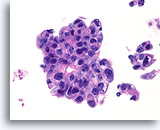

Ductaal carcinoom, Borst FNA, Celblok.

Kleine vergroting van de patiënt in afbeelding 65-66 toont de discohesieve monotone ductale celpopulatie met gerandomiseerde polariteit en een solide groeipatroon.

10X

Ductaal carcinoom, Borst FNA, Celblok.

Kleine vergroting van de patiënt in afbeelding 65-66 toont de discohesieve monotone ductale celpopulatie met gerandomiseerde polariteit en een solide groeipatroon.

10X

Ductaal carcinoom, Borst FNA, Celblok.

Er is duidelijk gerandomiseerde polariteit van een cytologisch atypische en vrijelijk stratificerende populatie ductale cellen aanwezig.

60X

Ductaal carcinoom, Borst FNA, Celblok.

Er is duidelijk gerandomiseerde polariteit van een cytologisch atypische en vrijelijk stratificerende populatie ductale cellen aanwezig.

60X